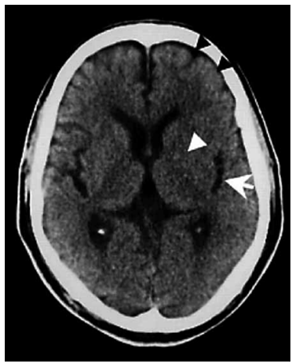

Paciente do sexo feminino, de 71 anos, portadora de

hipertensão arterial e dislipidemia, em uso irregular das

medicações, apresenta início súbito de hemiplegia direita

e afasia há 170 min. Chega ao pronto atendimento apresentando no exame físico: PA: 190 x 100 mmHg; FC:

92 bpm; FR: 20 irpm; SatO₂: 95%; NIHSS: 14 pontos.

Encaminhada para tomografia de crânio, que apresentou

a imagem a seguir:

(Arquivo pessoal; imagem usada com autorização)

Qual é a conduta imediata?